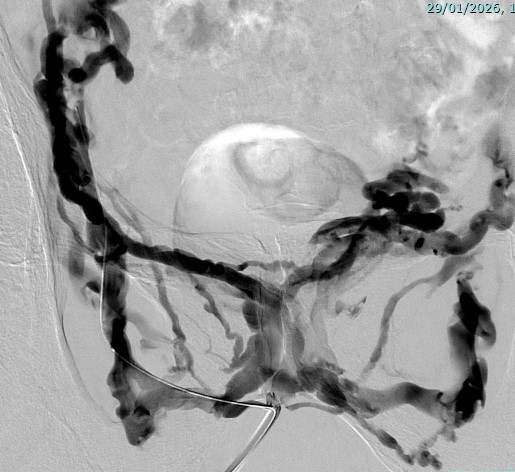

Angiographie de bilan par voie veineuse du petit bassin

Angiographie de contrôle après injection de Glubran et Lipiodol

Embolisation de celle-ci : de la colle biologique est injectée pour boucher la fuite.